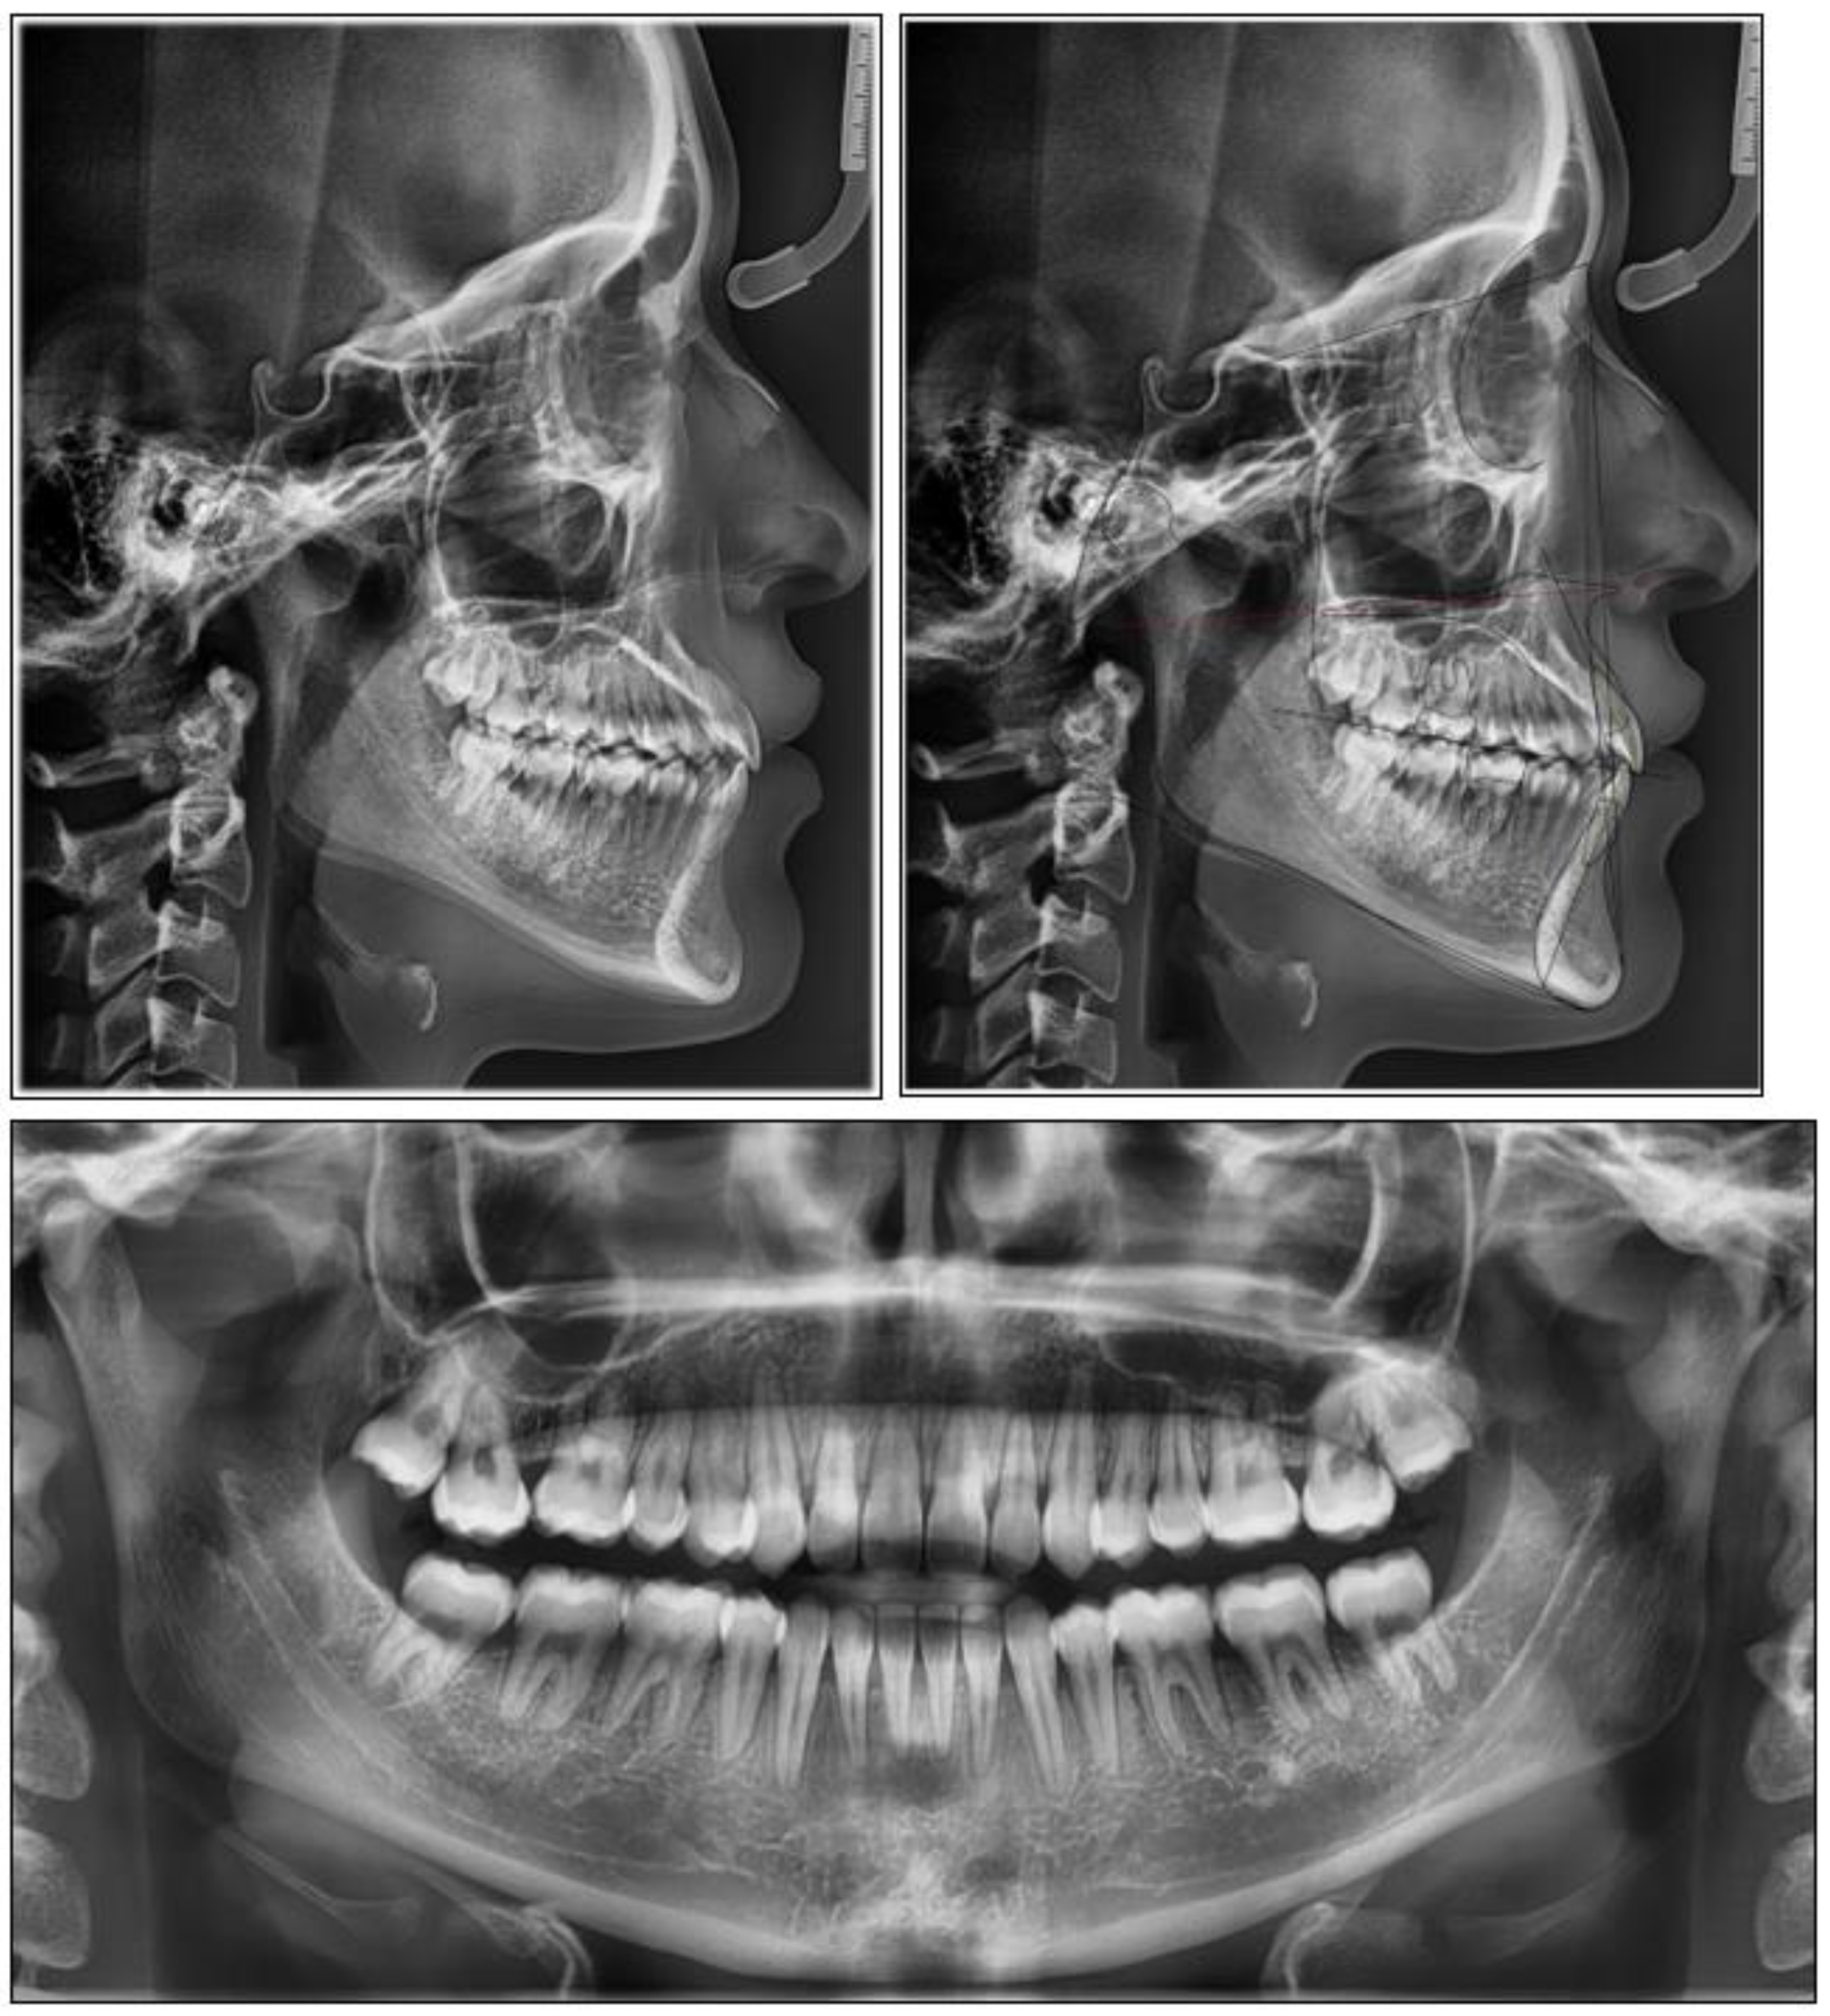

2. Case Report

2.2. Treatment Progress

3. Results

| Pretreatment | Post-treatment | |

|---|---|---|

| Sagittal Skeletal Relations | ||

| SNA | 74.2° | 74.8° |

| SNPg | 77.2° | 77.5° |

| ANPg | −3° | −2.7° |

| Wits | −9 mm | −9 mm |

| Vertical Skeletal Relations | ||

| SN/ANS-PNS | 5° | 3.6° |

| SN/Go-Gn | 39.7° | 38.8° |

| ANS-PNS/GoGn | 34.7° | 35.2° |

| Dento-Basal Relationts | ||

| I/ANS-PNS | 112.5° | 109° |

| i/GoGn | 88.7° | 87.6° |

| i/APg | +4.3 mm | +4.4 mm |

| Dental Relations | ||

| Overjet | +2 mm | +2 mm |

| Overbite | +1 mm | +2 mm |

| Interincisal Angle | 128.3° | 131.8° |